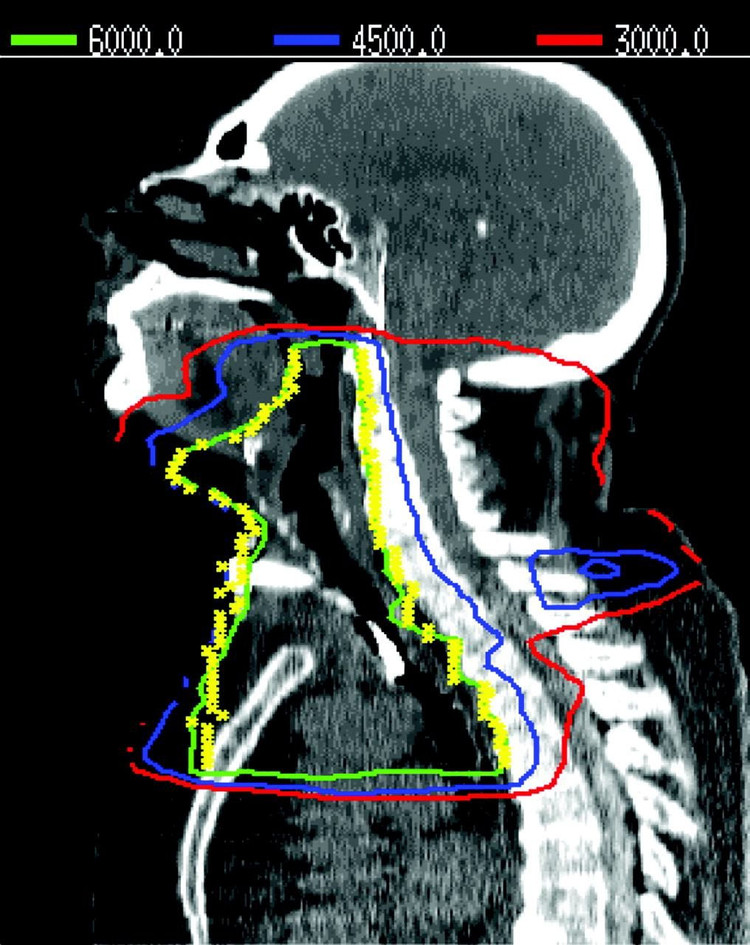

TS.BS Nguyễn Quang Bảy, Trưởng khoa Nội tiết và Đái tháo đường, Bệnh viện Bạch Mai: Tuyến giáp nằm ở nông và mô tuyến giáp rất nhạy cảm với tia xạ. Các nhà khoa học tại Đại học Lisbon, Bồ Đào Nha đã tiến hành một nghiên cứu hồi cứu trên 282 bệnh nhân được chiếu xạ ngoài vùng cổ, sọ não - tủy sống hoặc toàn bộ cơ thể để điều trị 4 nhóm ung thư chính gồm: bệnh bạch cầu, bệnh Hodgkin, ung thư hệ thần kinh trung ương và ung thư đầu cổ trong thời gian từ năm 1972 - 2005.

Kết quả: Có 56,7% bệnh nhân bị suy giáp, xuất hiện sau trung bình 6,8 ± 5,9 năm sau xạ trị. Chiếu xạ vùng cổ và sọ não - tủy sống làm tăng nguy cơ gây suy giáp gấp 3,5 lần so với chiếu xạ toàn thân. Ung thư tuyến giáp thể nhú được chẩn đoán ở 8,5% bệnh nhân (cao nhất ở nhóm ung thư bạch cầu và bệnh Hodgkin) sau trung bình là 18,5 ± 4,9 năm sau xạ trị. Giới tính nữ, tuổi trẻ hơn và liều chiếu xạ thấp (< 35 Gy) có liên quan (làm tăng gấp 3-5 lần) với xuất hiện ung thư tuyến giáp.